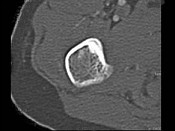

- 单项选择题男,28岁, 右上肢疼痛,夜间加重, 服用止痛药可缓解,结合图像, 最可能的诊断是 ( )

C、骨样骨瘤